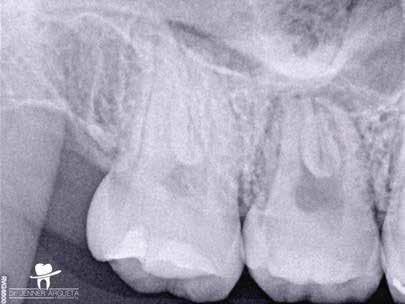

1. a–f ábrák: A cingulumon keresztül gömbfúróval kialakított hozzáférés a trepanációs kavitás labiális irányba történő túlzott mértékű kiterjesztését eredményezheti, és ez lényegesen növelheti a perforáció esélyét (a). A guttapercha átsejlik a lágyrészek alatt (b). Klinikailag igazolt perforáció (c). A preoperatív sagittális irányú CBCT-szeleten jól látható a labiális perforáció (d). Labiális irányú perforáció (fekete nyíl; e). A tényleges gyökércsatorna (piros nyíl; f).

2. a-b ábrák: A cingulumon keresztül gömbfúróval végzett trepanálás túlzott pericervikális dentin áldozattal, fordított tölcsér effektussal és perforációk kialakulásával járhat (fehér nyíl).

A frontfogakban történő hozzáférési nyílás kialakítása

A frontfogakban a hozzáférési nyílás kialakítását hagyományosan a fogak linguális vagy palatinális felszínén, a cingulumon keresztül egy gömbfúró segítségével kezdjük. A linguálisan elhelyezkedő kiemelkedés teljes eltávolítása, továbbá a pulpaszarvak teljes feltárása egy háromszög alakú hozzáférési nyílást eredményez. 7 Ezt a módszert a fogak esztétikai megjelenésének megőrzése érdekében fejlesztették ki. Ez azonban időnként a saját foganyag indokolatlan eltávolításával, a trepanációs kavitás labiális irányba történő túlzott kiterjesztésével, perforációval, valamint a fog kritikus helyen, a pericervikális dentin (PCD) területén történő meggyengítésével jár (1. a–f és 2. a-b ábrák). 19 Felmerült, hogy a pericervikális dentin rendkívül fontos szerepet játszik a rágóerő gyökerek irányába történő továbbításában, és elképzelhető, hogy a gyökérkezelt fogak hosszú távú megtartása szempontjából a legfontosabb tényező az ép pericervikális dentin megőrzése lehet. 20 A cingulumon keresztül történő hozzáférési nyílás

kialakítása során fennáll a fog labiális irányú perforációjának veszélye, mivel ilyenkor a foganyag elvételét labiális irányú fúrótartással kezdjük. Nemrégiben újragondolták a